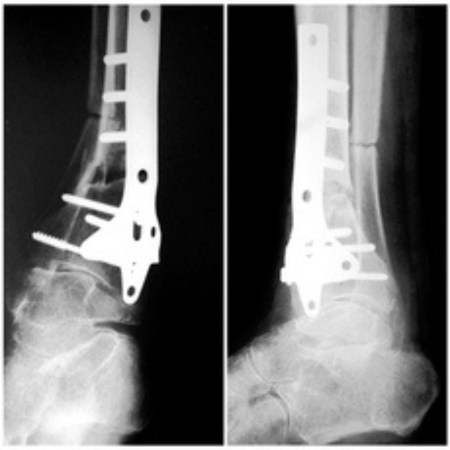

♦ Незараснали и неправилно зараснали счупвания: Предлага възстановителни и реконструктивни операции при неправилно зараснали или незараснали счупвания на крайниците.

♦ Ходилни деформации: Диагностицира и лекува вродени (пес еквиноварус) и придобити деформации на ходилата – плоскостъпие, халукс валгус, метатарзоварус и др.